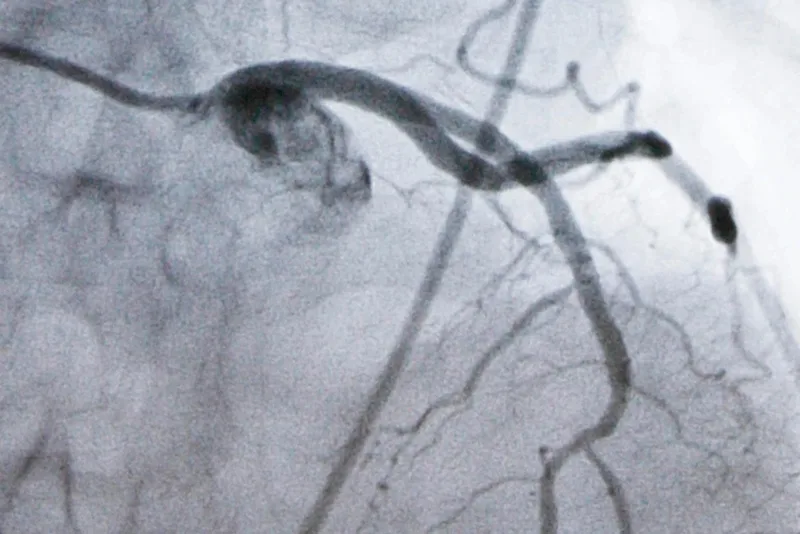

Heart disease is the nation’s leading cause of death and high LDL cholesterol, which causes plaque to build up in arteries, is a top risk factor for heart attacks and strokes. While an LDL level of 100 is considered fine for healthy people, doctors recommend lowering it to at least 70 once people develop high cholesterol or heart disease — and even lower for those at very high risk.